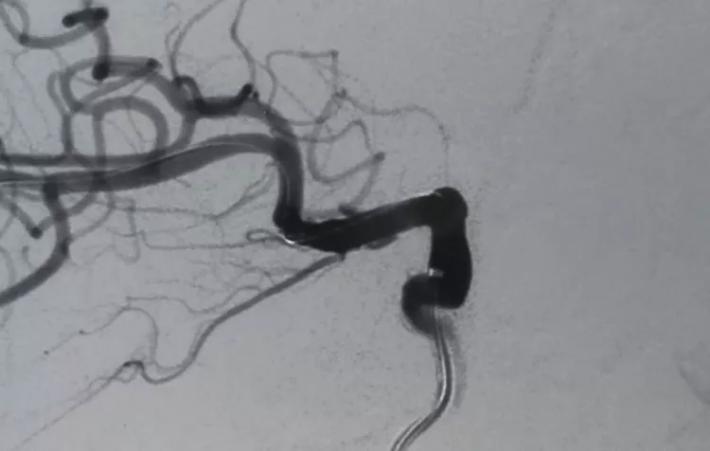

释放支架后见BBA显影变浅,仅后半部分晚期显影,脉前A显影好,再次后扩。

二次后扩后颈内动脉造影见BBA逆向充盈部分显影,晚期仍有造影剂滞留,如远端再次叠套一支架必会累及脉前A,2周后复查DsA吧,希望BBA不破而且血栓自愈。

蒙片看支架释放成形很好,远端由于脉前A的原因覆盖的较短,故而有少量逆向渗漏,但是蒙片看造影剂晚期滞留明显,与家属沟通后终止手术! 2周后切线位DsA造影可看到造影剂充盈BBA,造影剂与支架间形成一充盈平面,与术后DsA形态比较明显增大,而且M1有明显的痉挛。